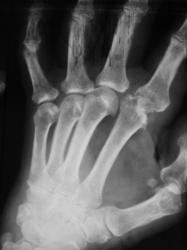

Катенёв Валенти... Дата публикации 03.07.2009, 23:53 Пациент направлен в рентгеновский кабинет "для рентгенографии кистей" терапевтом с диагнозом "Ревматоидный артрит". Произведены рентгенограммы. Ваше мнение коллеги? Сб, 04/07/2009 - 00:59 #1 Петрович Не на сайте Был на сайте: 7 лет 2 месяцев назад Зарегистрирован: 22.03.2009 - 01:13 Публикации: 3908 Для полноценной диагностики "Ревматоидного артрита" маловато представлено костей запястья. А из того, что представлено видна Подагра. Или нет? Неоднозначно всё Сб, 04/07/2009 - 12:12 #2 Ермолаев Не на сайте Был на сайте: 8 лет 10 месяцев назад Зарегистрирован: 07.02.2009 - 16:33 Публикации: 670 Соглашусь с мнением Петровича! Больше похоже на подагрический артрит. dok Вс, 05/07/2009 - 01:12 #3 OPEXOB Не на сайте Был на сайте: 9 лет 11 месяцев назад Зарегистрирован: 26.07.2008 - 10:02 Публикации: 280 Господа, мнения разделились. Поясните, кто что видит, а не окончательный диагноз. Подагра? где тофусы, "пробойники". Вс, 05/07/2009 - 12:31 #4 Ермолаев Не на сайте Был на сайте: 8 лет 10 месяцев назад Зарегистрирован: 07.02.2009 - 16:33 Публикации: 670 Коллега Орехов! Мнения, как раз и не разделились, а сошлись в одном - подагра. dok Вс, 05/07/2009 - 15:50 #5 alexey.krasnov Не на сайте Был на сайте: 10 лет 3 месяцев назад Зарегистрирован: 19.05.2009 - 10:52 Публикации: 30 Абсолютно согласен с Др. Ермолаевым и остальными. Bis Dat Qui Cito Dat

Для полноценной диагностики "Ревматоидного артрита" маловато представлено костей запястья. А из того, что представлено видна Подагра. Или нет?

Подагра? где тофусы, "пробойники".